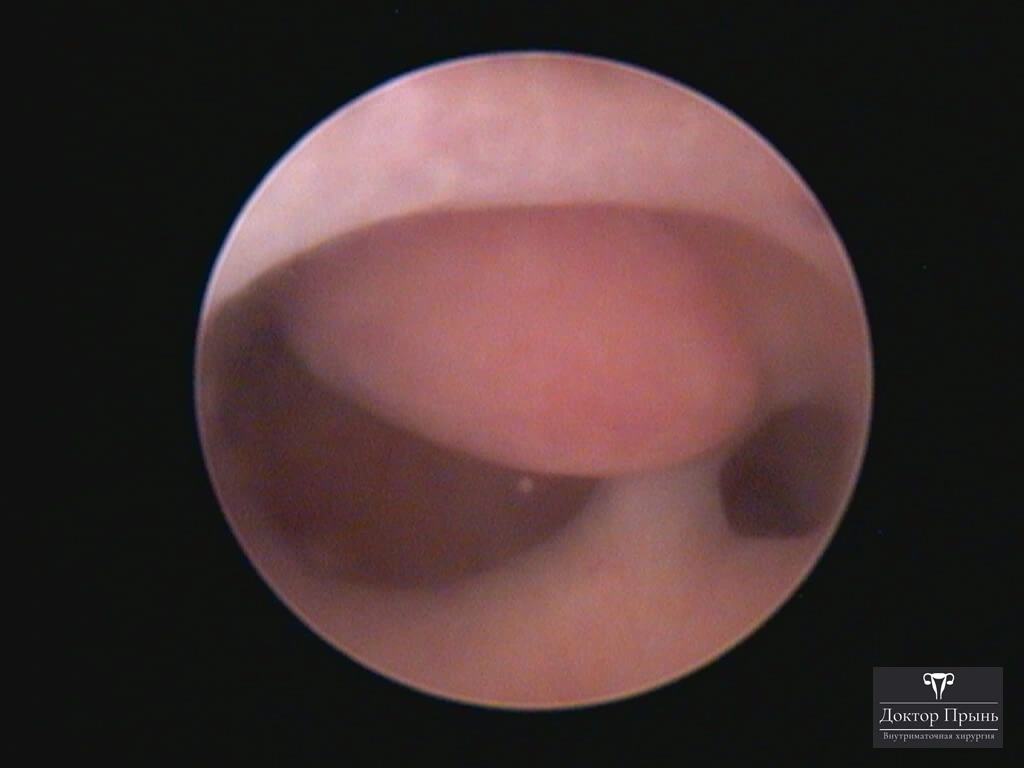

Фотогалерея

Синехии, рассечённые Прынь Д.В.

Гистероскопия позволяет не только увидеть спайки, но и сразу вылечить, т.е. рассечь их. Большинству пациенток подойдёт офисная гистероскопия без наркоза и госпитализации. Среднее время операции 15 минут. Иногда требуется 2-4 операции, чтобы восстановить полость матки.

Крайне важен способ разделения спаек. Если это холодный инструмент, например, ножницы, то вероятность рецидива низкая. Плюс не повреждается нормальный эндометрий. Если рассекают горячей электропетлёй, то, наоборот, риск рецидива высокий и можно обжечь эндометрий.